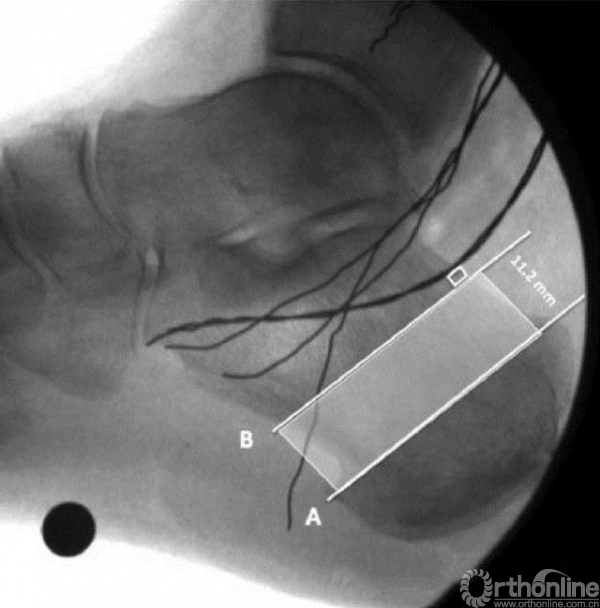

A线是标志线,显示自跟骨结节后上方向跖筋膜起点处走行

B线是A线的平行线,距最靠后的神经后方2mm,A线到B线之间的区域为安全区(图中阴影区)

1. 安全区域位于标志线近端(前方)11.2±2.7 mm

2. 该安全区为跟骨截骨避免损伤足底内外侧神经和腓肠神经提供参考依据